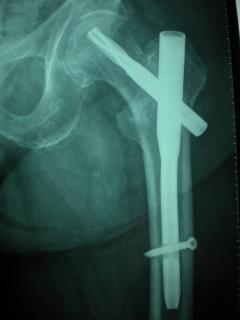

Περίπτωση 4ου ασθενούς

Με τα σύγχρονα μέσα που διαθέτουμε, όλα σχεδόν αυτά τα κατάγματα πρέπει να αντιμετωπίζονται χειρουργικώς. Υπάρχει πληθώρα υλικών οστεοσύνθεσης (πλάκες διαφόρων τύπων, ενδομυελικοί ήλοι, συστήματα εξωτερικής οστεοσύνθεσης) που είναι διαθέσιμα και επαφίεται στην εμπειρία του χειρουργού η επιλογή.

Οπως και άλλοι εξοικειωμένοι χειρουργοί διεθνώς, χρησιμοποιώ τεχνικές ελάχιστης παρέμβασης (Minimal Invasive Surgery), δηλαδή μικρές τομές, επειδή έτσι το χειρουργικό τραύμα είναι ελάχιστο, με αποτέλεσμα ταχύτερη επούλωση. Ταχύτερη πώρωση των καταγμάτων, ταχύτερη κινητοποίηση.

Όλες οι φωτογραφίες ολες προέρχονται από το προσωπικό αρχείο του κου Μ. Τυλλιανάκη